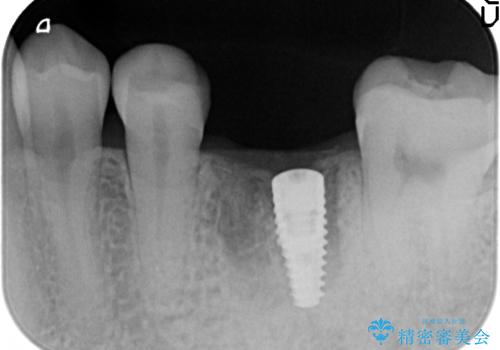

インプラント 割れてしまった歯の治療

- 左下6の歯で咬むと痛みがあり、たまに膿も出てくるので診て欲しいといらっしゃった方の症例です。

被せ物を外したところ歯が割れており保存不可能だったため抜歯し、インプラントによる欠損補綴を行いました。